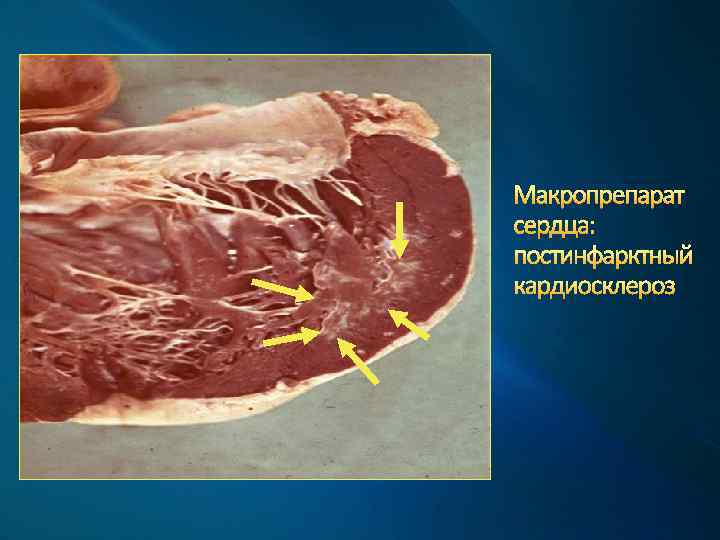

Макропрепарат сердца: постинфарктный кардиосклероз